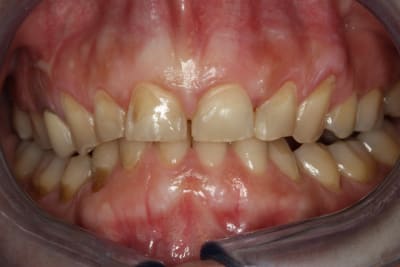

Bonjour,ma patiente présente des érosions des faces vestibulaires et est gênée esthétiquement car elles se colorent en quelques semaines après un détartrage et polissage. Elle me dit qu'elle serre les dents la nuit mais ne bruxe pas ( du moins son mari n'entend rien...). Au niveau alimentaire, il n'y a pas une consommation excessive de fruit, crudité, ni de boisson sucrée gazeuse. Ces érosions sont elles du au fait que la patiente serre les dents? Peut on envisager de les reconstituer avec des facettes ou est ce plutôt contre indiqué dans son cas? Merci pour vos conseils.

je suis quand même étonné qu'elle ne bruxe pas compte tenu des usures des bords libres antérieurs et des encoches en particulier 13 et facette abrasion versant V de 34.

en faisant bien attention à l'occlusion et aux trajets des contacts par rapport aux bords de collage des facettes, je pense qu'il n'y a pas de contre indication à la facette. prévoir peut être une gouttière de protection nocturne.

Chez nous on dit "abfraction" et 90% du temps problèmes occlusaux, faut simplement analyser le schéma occlusale

A ce stade il faut recouvrir, sinon le brossage va aggraver la situation (l’abrasif du dentifrice quel qu’il soit), il y a souvent une surcharge et/ou un déséquilibre occlusale (suite à ortho pourquoi pas) ce qui donne de l'abfraction, puis les facteurs locaux: brossage, soda, jus de fruit, rgo, dépôt bactérien... aggravent la situation. En l'absence d'un diagnostic précis, et si ce n'est pas Laure Manaudou, commencer par des composites et voir.

- le bruxiste est un athlète des atm, qu'il a fréquemment des tori osseux, qu'il use partout, plutôt à plat

- le chimique creuse et conserve de l'émail en bordure, l'attaque chimique va plus vite que l'usure de l'émail périphérique, il n'y a pas concordance entre la lésion (le fond) et la dent antagoniste

-le contraint use où il est bloqué pour se libérer, il y a concordance antago lésion, souvent les dents ont des formes très aiguisées.

Dans ton cas, sur les photos il semble y avoir un recouvrement incisif excessif, d'où surpression en propulsion, il faudrait aussi voir si elles ne sont pas (11 et 21, en fait le bloc incisivo-canin) trop lingualées, cela pourrait expliquer les deux fêlures verticales de l'émail.

La facette d'usure sur la 43 très marquée par rapport aux collatérales postr... le bloc antr mandibulaire appuie fort (c'est un contraint?).

Si tu fais des facettes tu risques d'avoir les même fêlures en vestibulaire ou pire, il faudrait tester ou "libérer" la mandibule, si quelqu'un a une idée?